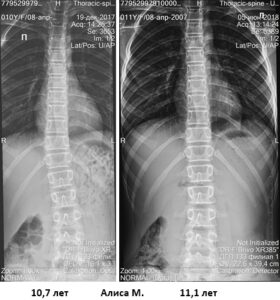

Коррекция в детском возрасте

image004

image006

2018 07 06 merzlenko